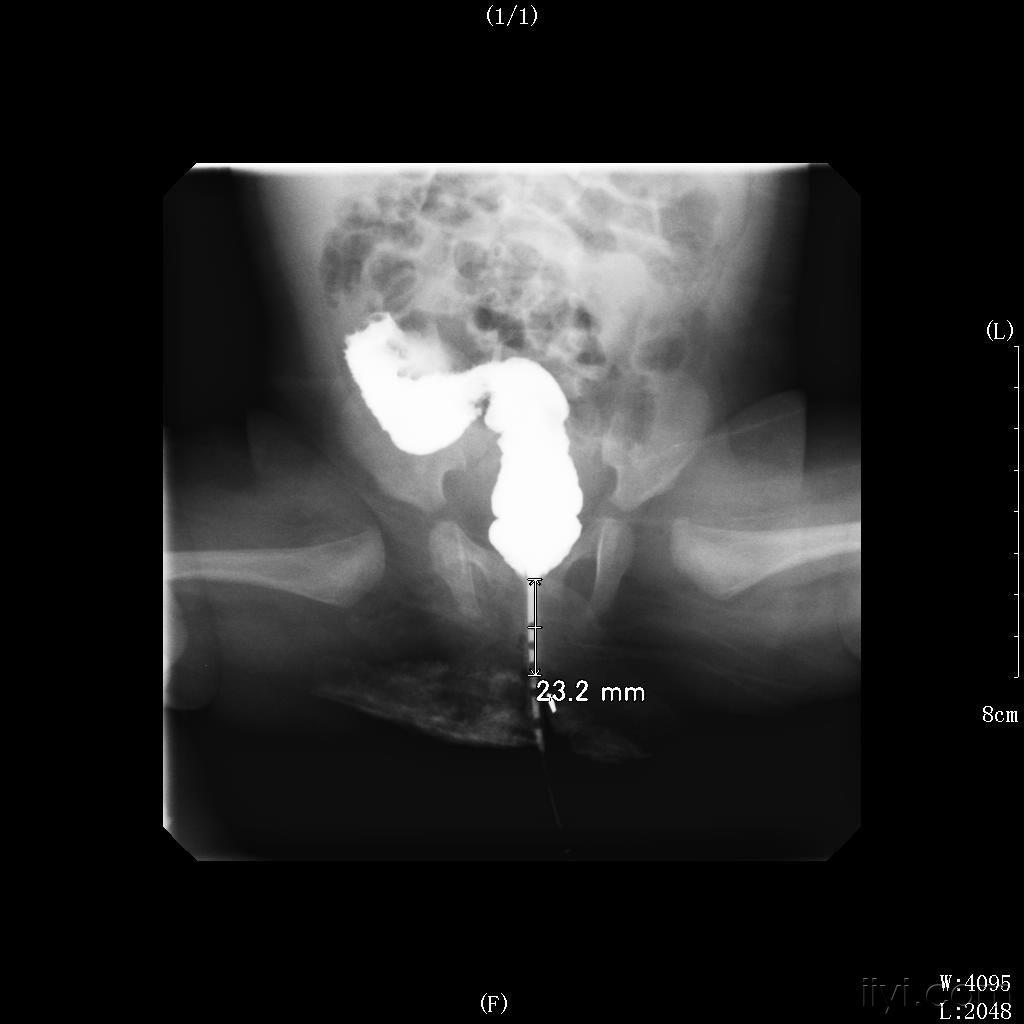

超声诊断低位肛门闭锁并尿道直肠瘘1例

【原创】先天性肛门闭锁并舟状窝瘘